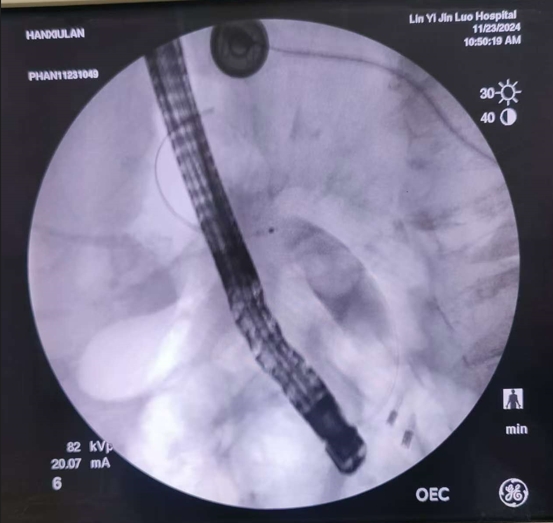

昨日在全程的精心監(jiān)護下,為了做到更安全、萬無一失,姜開通主任還邀請了市醫(yī)院的曾憲忠主任共同參與,為老人實施了內(nèi)鏡下的逆行膽管造影治療術,病人年齡超高,出現(xiàn)乳頭處憩室,遇到困難,兩位主任憑多年經(jīng)驗及超高手法,較為順利給予病人做了微創(chuàng)治療,術后老人的生命體征非常平穩(wěn),沒有任何不適,今日查房患者和家屬都感到非常滿意和感激。